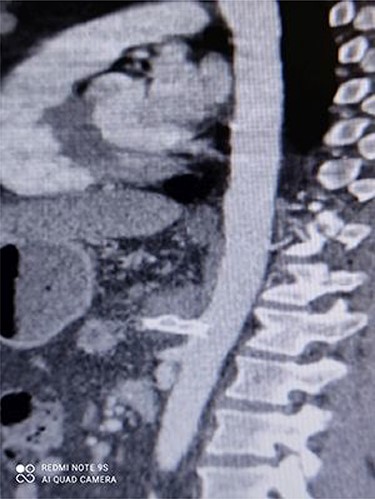

CT angiography revealed a saccular aneurysm in the right trunk of the celiac artery (42*56*59 mm) with thrombus formation lining its wall. The aneurysm lumen was patent and had a diameter of 20*21*34 mm. With a 12-mm patent neck, the aneurysm was connected to the main artery. The aneurysm was surrounded by distal branches of the left gastric, common hepatic and splenic arteries. A percutaneous angiographic intervention was suggested to the patient, and he was asked to go to NPO from midnight. After prepping and draping, a right femoral artery puncture was performed under local anesthesia, and a 6 French angiographic sheath (Arrow®) was inserted. The 6 French JR catheter (Alvision™) was extended to the aorta via a hydrophilic wire (AqWire®) and contrast media was injected, revealing a celiac artery aneurysm. The 8F*40 (Arrow®) sheath was then replaced, and the celiac artery was cannulated, and two 40*10 and 40*9 mm covered stents (Fluency™) were inserted through a stiff park wire (Amplatz Emerald). Finally, good results were obtained, with full aneurysmal coverage and distal celiac artery patency. Three days after the patient was admitted to the ward, a CT angiography revealed good results with complete coverage of the aneurysmal area and no leakage.

Figures 3 and 4 show CT angiography findings after the endovascular intervention.